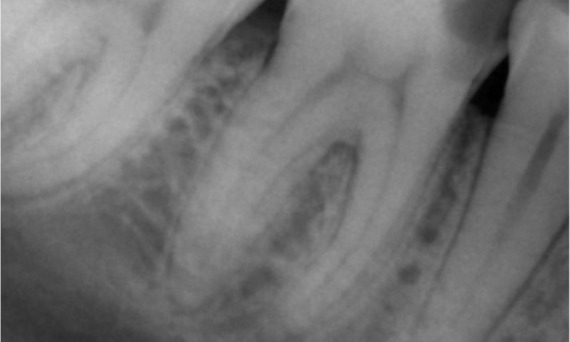

Avant : L’examen a révélé une lésion carieuse liée à la première molaire mandibulaire droite. L’examen radiographique a révélé la proximité de la lésion avec la corne pulpaire et, en l’associant à la plainte principale, un diagnostic final de pulpite chronique irréversible a été posé.

Après : La cavité d’accès a été réalisée de la manière la plus conservatrice possible. TruNatomy a été le système de choix en raison de l’âge du jeune patient. Nous devions préserver la dentine autant que possible afin d’augmenter la capacité de la dent à surmonter la charge occlusale et d’accroître la longévité de la restauration finale.